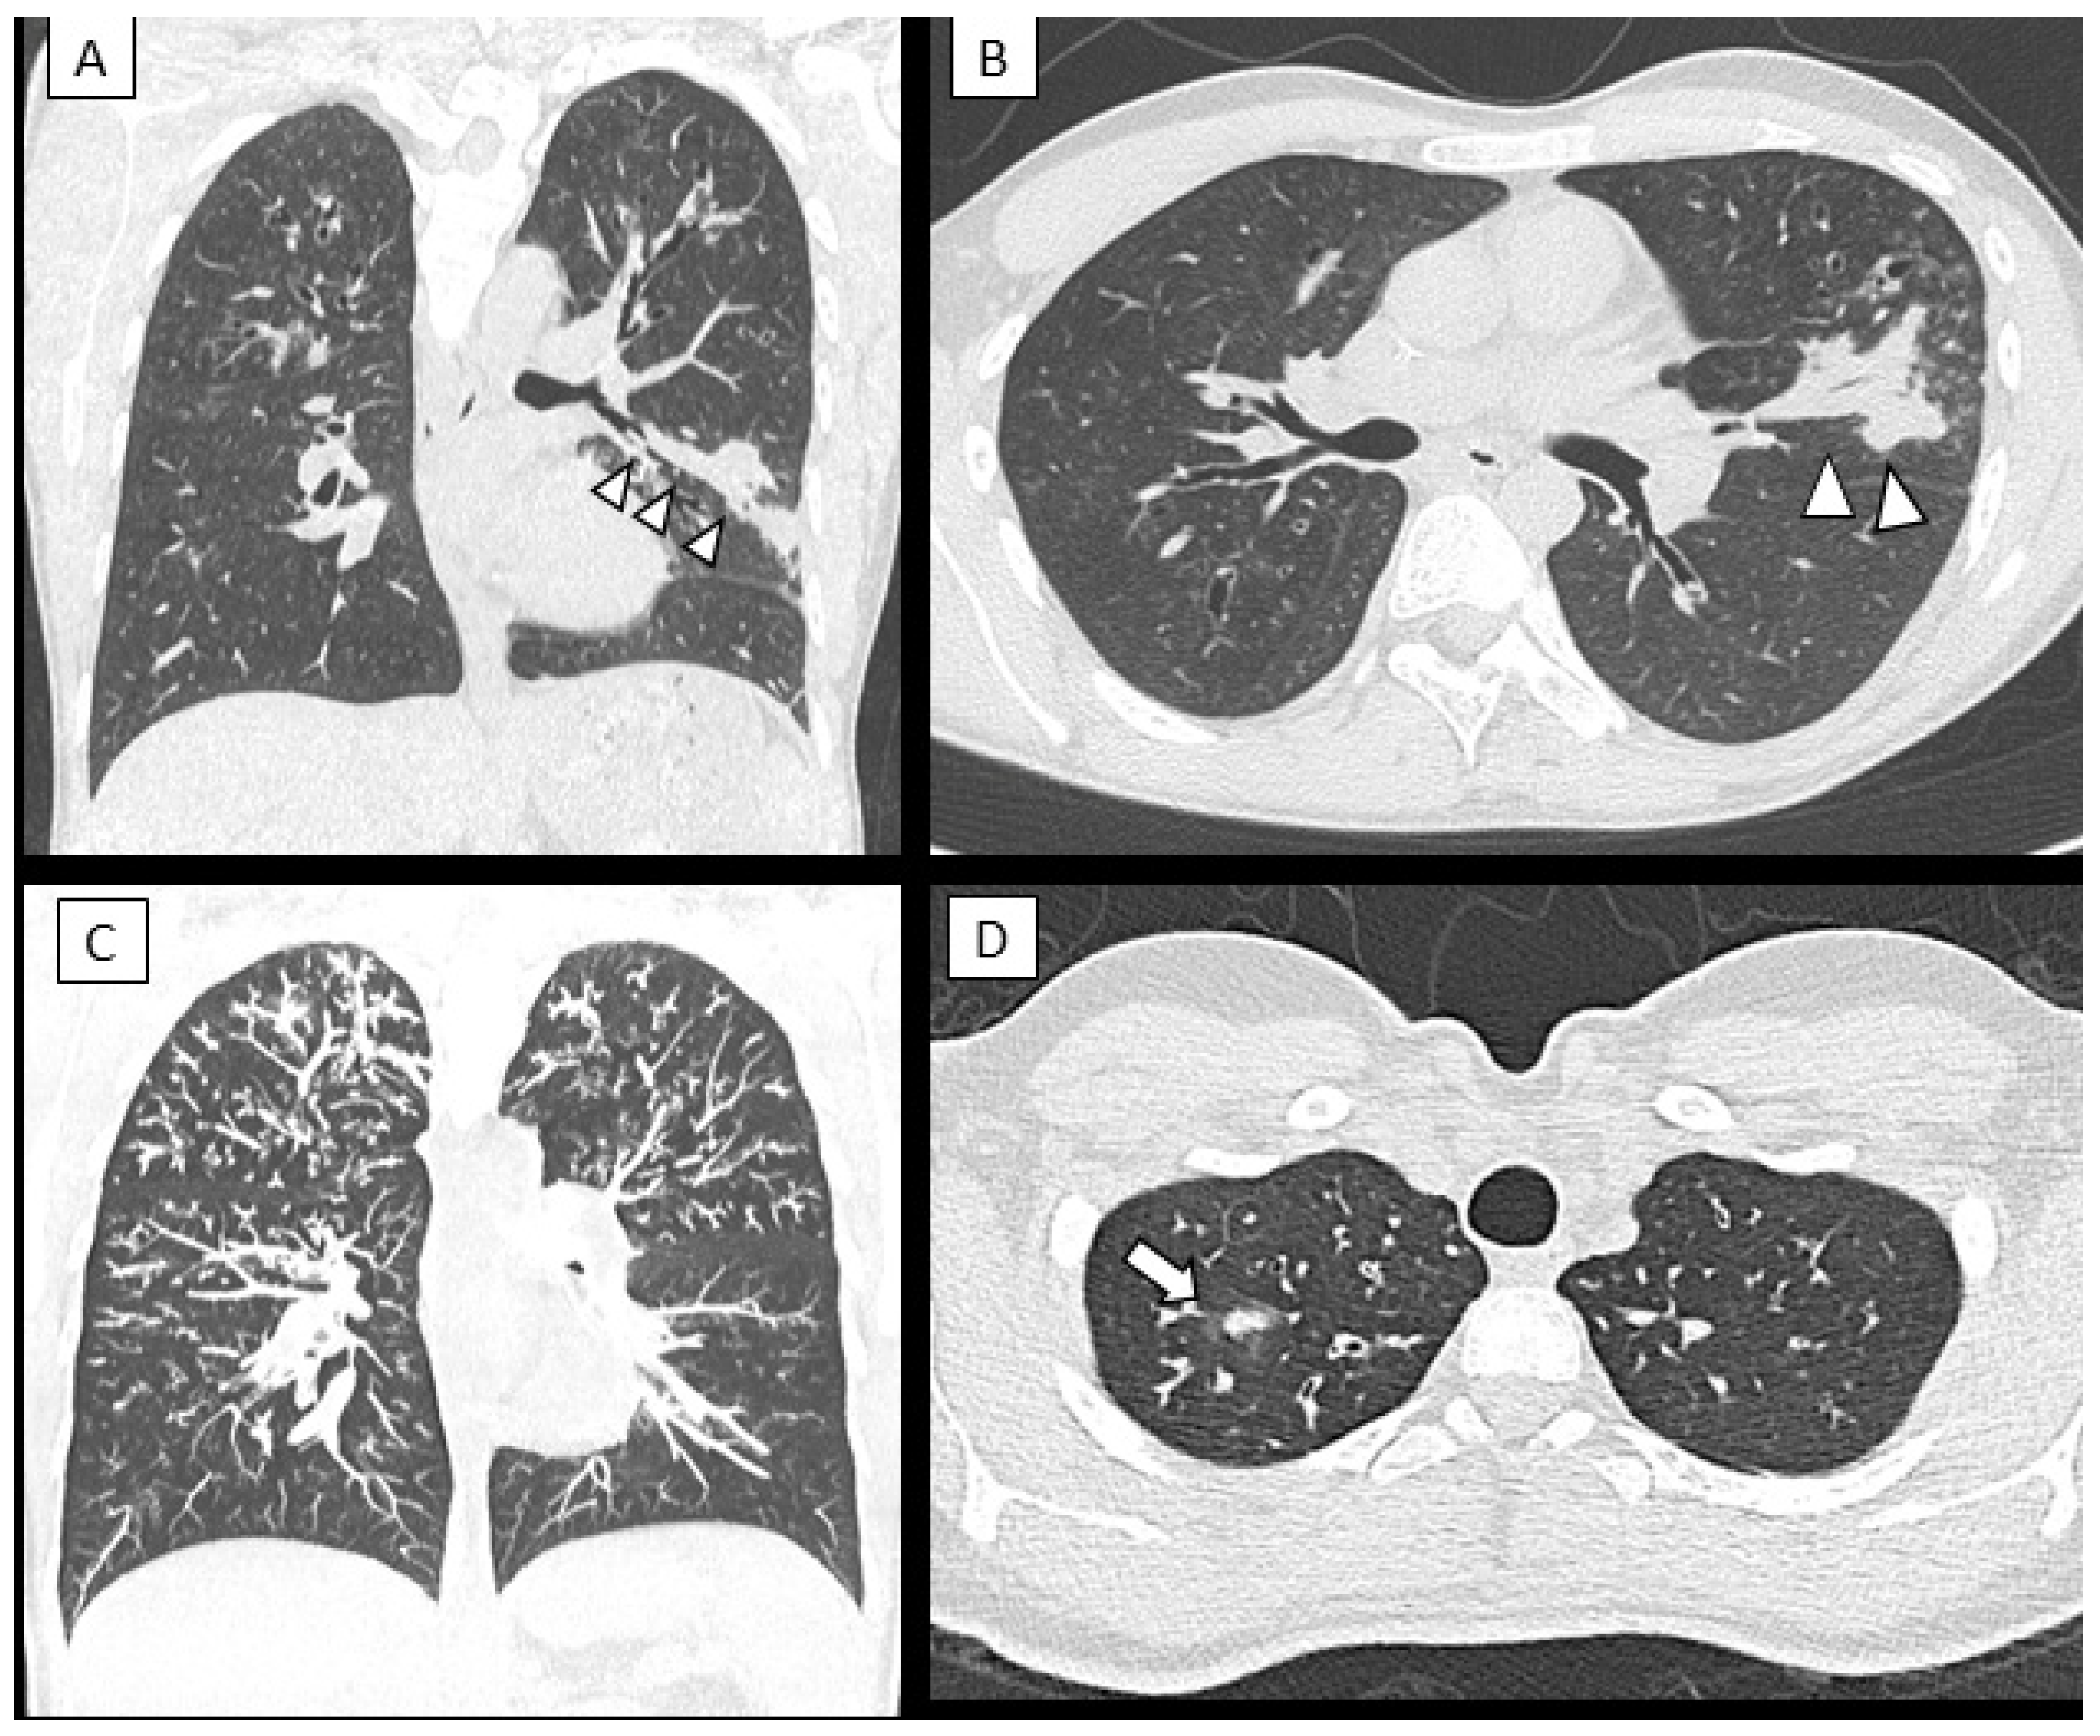

HRCT scans were available for 29 out of 38 patients (76.3%), of which six had ABPA, and eight were sensitized to Af. Compared to patients with no signs of Af, patients with ABPA and patients sensitized to Af showed more abnormalities in lung structure (Bhalla scores: ABPA 14 ± 3.6, Af sensitization 17.1 ± 5.8, non-Af patients 22.2 ± 2.8; p < 0.005). Figure 4 shows typical radiological features found in ABPA patients.

Figure 4.

CT findings of mucus plugging: multi-planar reconstruction (MPR) in a coronal (A) and axial oblique plane (B) of a 17-year-old boy. The “finger in glove sign” (arrowheads) can be seen in the lingual region; this sign is consistent with large airway mucoid impaction, frequently seen in ABPA. Other parenchymal and airway abnormalities are seen in the apical regions of the lungs (cylindrical bronchiectasis and nodular consolidation). Coronal maximum intensity projection-MIP (C) and axial plane CT images (D) of a 16 year-old female with ABPA shows diffuse branched opacities in the upper lung regions, so called “tree in bud appearance” representing distal airways mucus plugging. Small consolidation in the apical segment of the right upper lobe is also seen (white arrow).